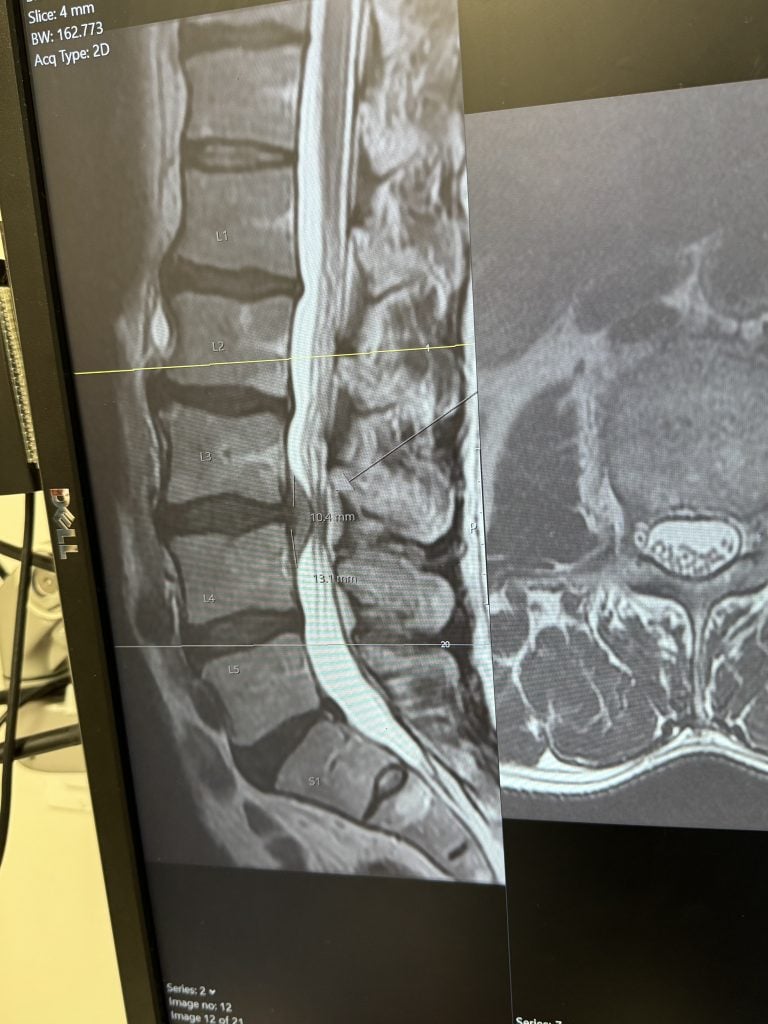

Microdiscectomy: Minimally Invasive Surgery for a Herniated Disc

After two years of living with a herniated disc, I had a microdiscectomy at HSS. The entire experience was smooth and well-organized. Dr. Bernard Rawlins performed the surgery, and his secretary, Delisabeth, was exceptional in helping me schedule appointments around my college schedule. The team was attentive and caring, and their follow-up system is outstanding - they check in on you even years later to ensure you’re doing well. I couldn’t have asked for better care.